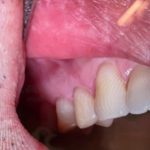

上のお写真の患者様は前歯の隙間を気にしていらした女性の方です。

なるべく削らずに治療を進めたいということがご希望でした❣️

矯正などもあるとは思いますが

当院では接着療法を選択させていただきました♪

今回のは処置は完全非切削で全て成し遂げております。💕🥰

この処置はおすすめです😁唐揚げでもなんでも硬いものも食べて頂いてオッケーです💁♀️